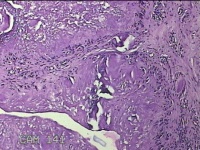

左外踝包块

性别

男

年龄

31岁

临床诊断

皮下结节

一般病史

发现左外踝包块1年余。

标本名称

大体所见

灰白暗红色包块1.8x1.3x0.7cm一个,表面糜烂,切开包块,内见大量石灰样物,内壁粗糙。

去了解病史,应该是痛风结节。